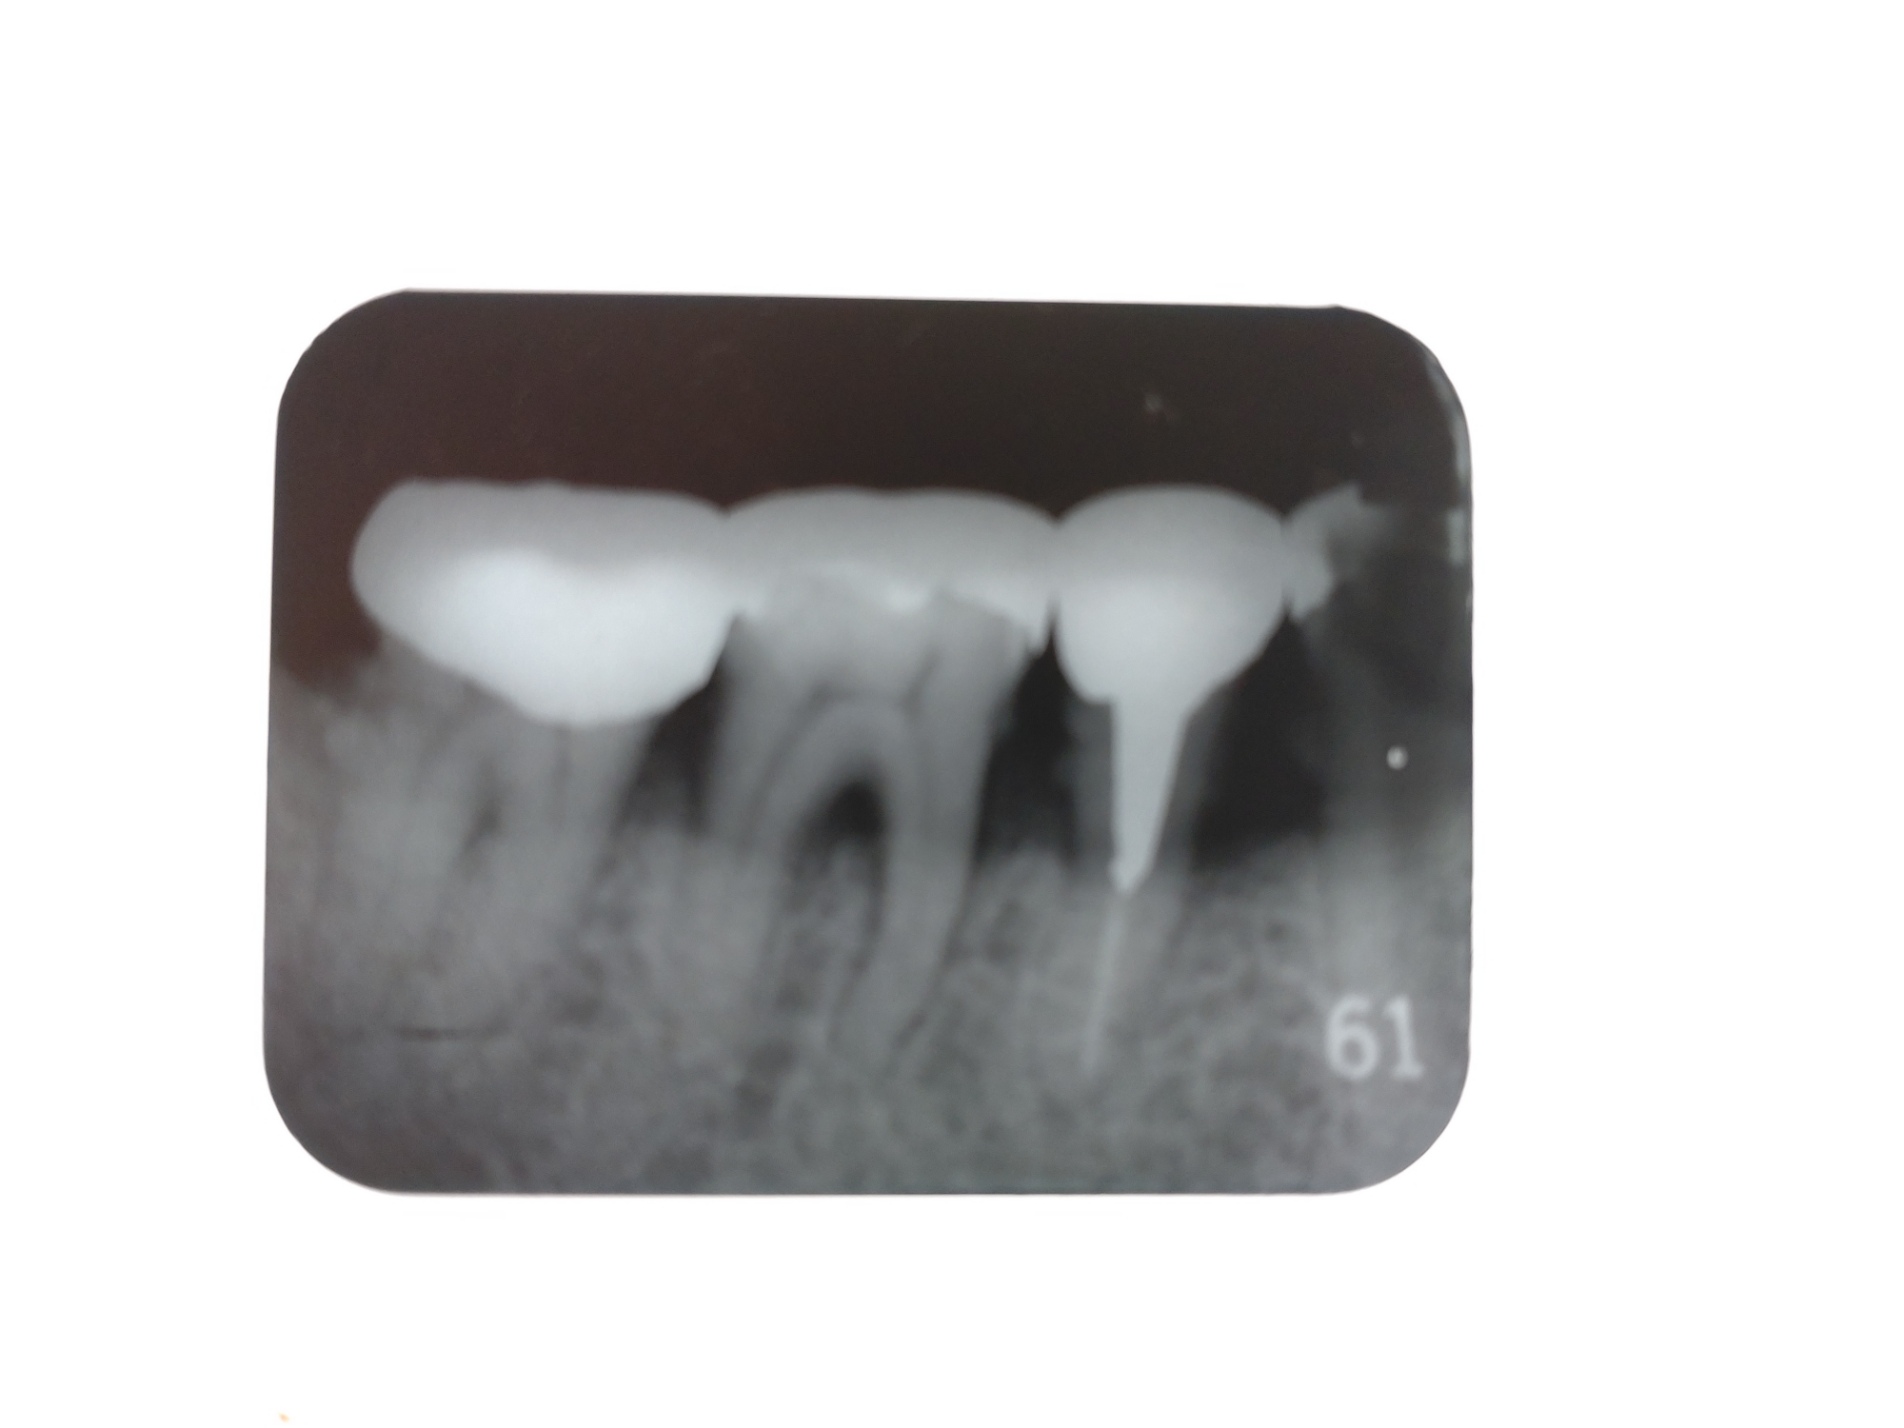

歯科の受診時には、ほとんどの場合レントゲン撮影を行います。

治療をする上で、虫歯や歯周病において歯の内部や歯肉の中、その下部の骨(歯槽骨)の中の状況を把握することは診断および治療には欠かせません。

多くの歯科医院また当院でも、大きい顎全体を撮影するパノラマと小さいフィルムで特定の歯を撮影するデンタルの2種類を撮影することが多いと思います。

パノラマは上下の顎全体鼻腔なども含めて撮影され全ての歯の並び、状態、歯槽骨の状態、顎骨内部の病変などを確認するものです。

デンタルは、サイズが小さく3~4歯並んだ部分を対象として、パノラマよりもより細かな情報を得るために虫歯の発見や診断の為に撮影されるものです。

歯科のレントゲン撮影は、パノラマの1回の撮影で約0.04mSv、デンタルでは0.02mSvでさらに微量です。

何年かぶりに撮影して以前のレントゲン写真と比較して虫歯や歯周病などの変化や新たな病変を発見したり、治療中にその評価の為の撮影など、早期発見・早期治療や診断には必要なものであり、ひいては治療期間や回数の短縮、治療によって受けるストレスの軽減に繋がると思います。